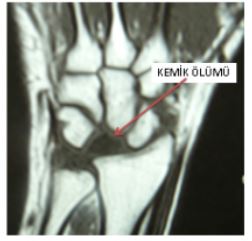

Direkt grafiler ulnar varyans, karpal yükseklik, radial inklinasyon ve dejeneratif değişikliklerin değerlendirilmesi açısından son derece önemlidir. Ulnar varyansın tam olarak değerlendirilmesi için omuz 90°, dirsek 90° ve önkolun nötral pozisyonda olması önemlidir. Hastalığın başlangıcında direkt grafiler tamamen normaldir, daha sonra lunatumda yaygın skleroz ortaya çıkar. Hastalığın ilerleyen dönemlerinde lunatumda çökme oluşur, bunu kapitatumun yukarıya yönlenmesi, skafoidin yer değiştirmesi ve sonrasında hızla gelişen yaygın artroz bulgularının ortaya çıkması takip eder. Manyetik rezonans görüntüleme (MRG) direkt radyolojik bulguların olmadığı hastalığın erken dönemlerinde etkilidir. Özellikle Ti ağırlıklı kesitlerde düşük sinyal intensiteleri, T2 ağırlıklı kesitlerde ise hiperintens görünüm izlenir (Şekil i).

En sık Lichtman'ın radyolojik bulgulara göre tanımlamış olduğu sınıflandırma kullanılmaktadır (Tablo 1). Birinci evrede direkt grafiler normaldir, fakat MRG'de difüz sinyal intensite değişiklikleri vardır. İkinci evrede direkt grafilerde lunatumda difüz skleroz vardır. Üçüncü evre ikiye ayrılır: Evre IIlA'da lunatumda çökme vardır (genellikle hastalığın ilk tanımlandığı dönemdir). Evre IIIB'de lunatumdaki çökmeye kapitatumun proksimale yer değiştirmesi ve sakafolunat açının 60°'nin üzerine çıkması ile karpal yükseklik azalması eşlik eder. Evre IV'de lunatumdaki çökmeye radiokarpal ve midkarpal artroz eşlik eder (Tablo 1).